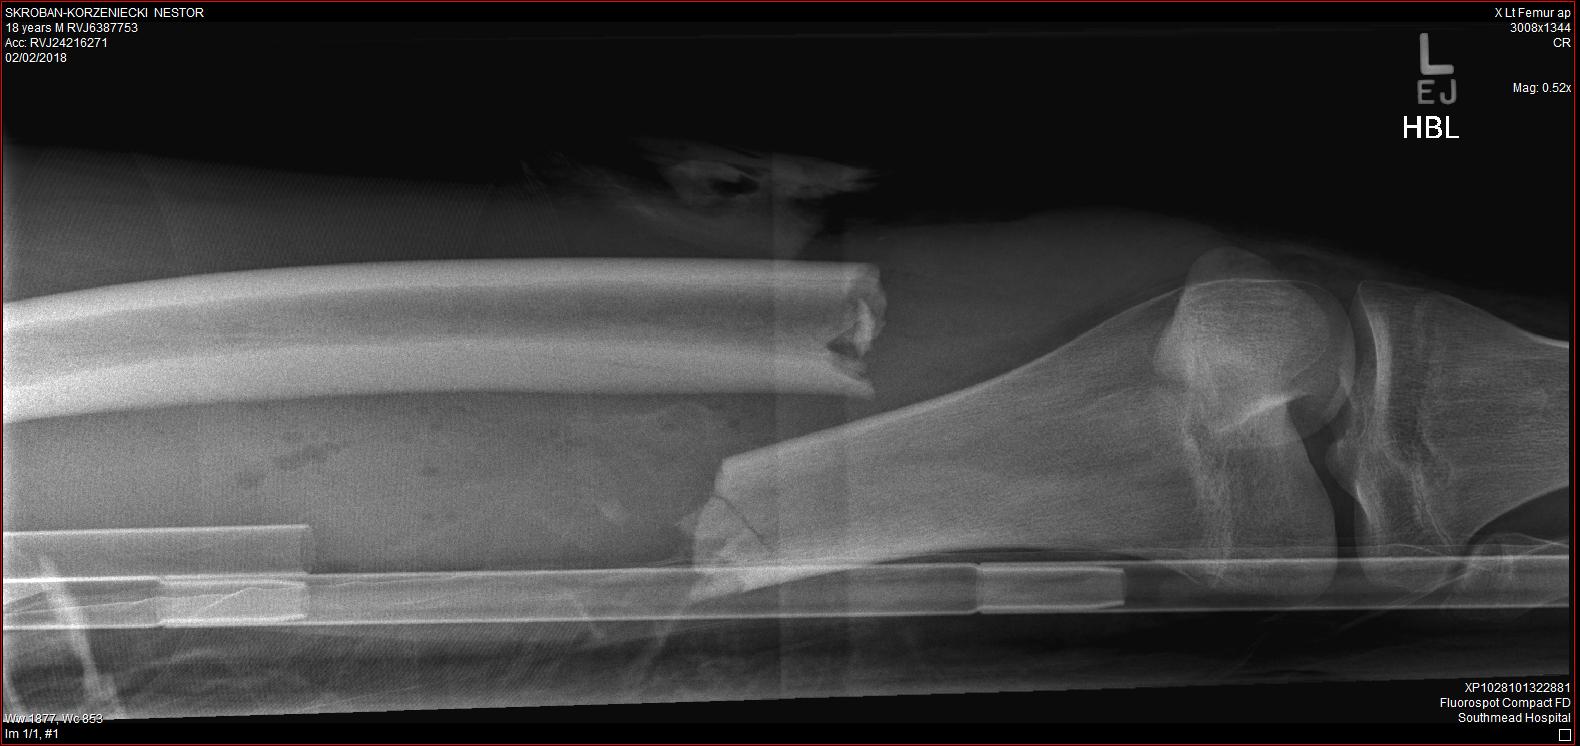

I received a place in Gloucestershire College, Coleford Campus, where I studied Art and Design Level 2 for a year before moving on to Level 3 for two years during which, on 2 February 2018, I was involved in a road traffic collision on my moped with a 73-year-old woman in her car. This resolted in a metal rod to be put in the broken left femur, a screw in the top part near the hip and three screws in the knee.

I spent three weeks in Southmead Hospital, including 9 days in a medically induced coma, in Bristol and a week in Gloucestershire Royal Hospital. During that time, my art and design teacher and general amazing person – Katie, set up a fundraiser with the help of my entire class. My parents bought a painting in that fundraiser that Katie did and my parents still have it framed up in the kitchen.